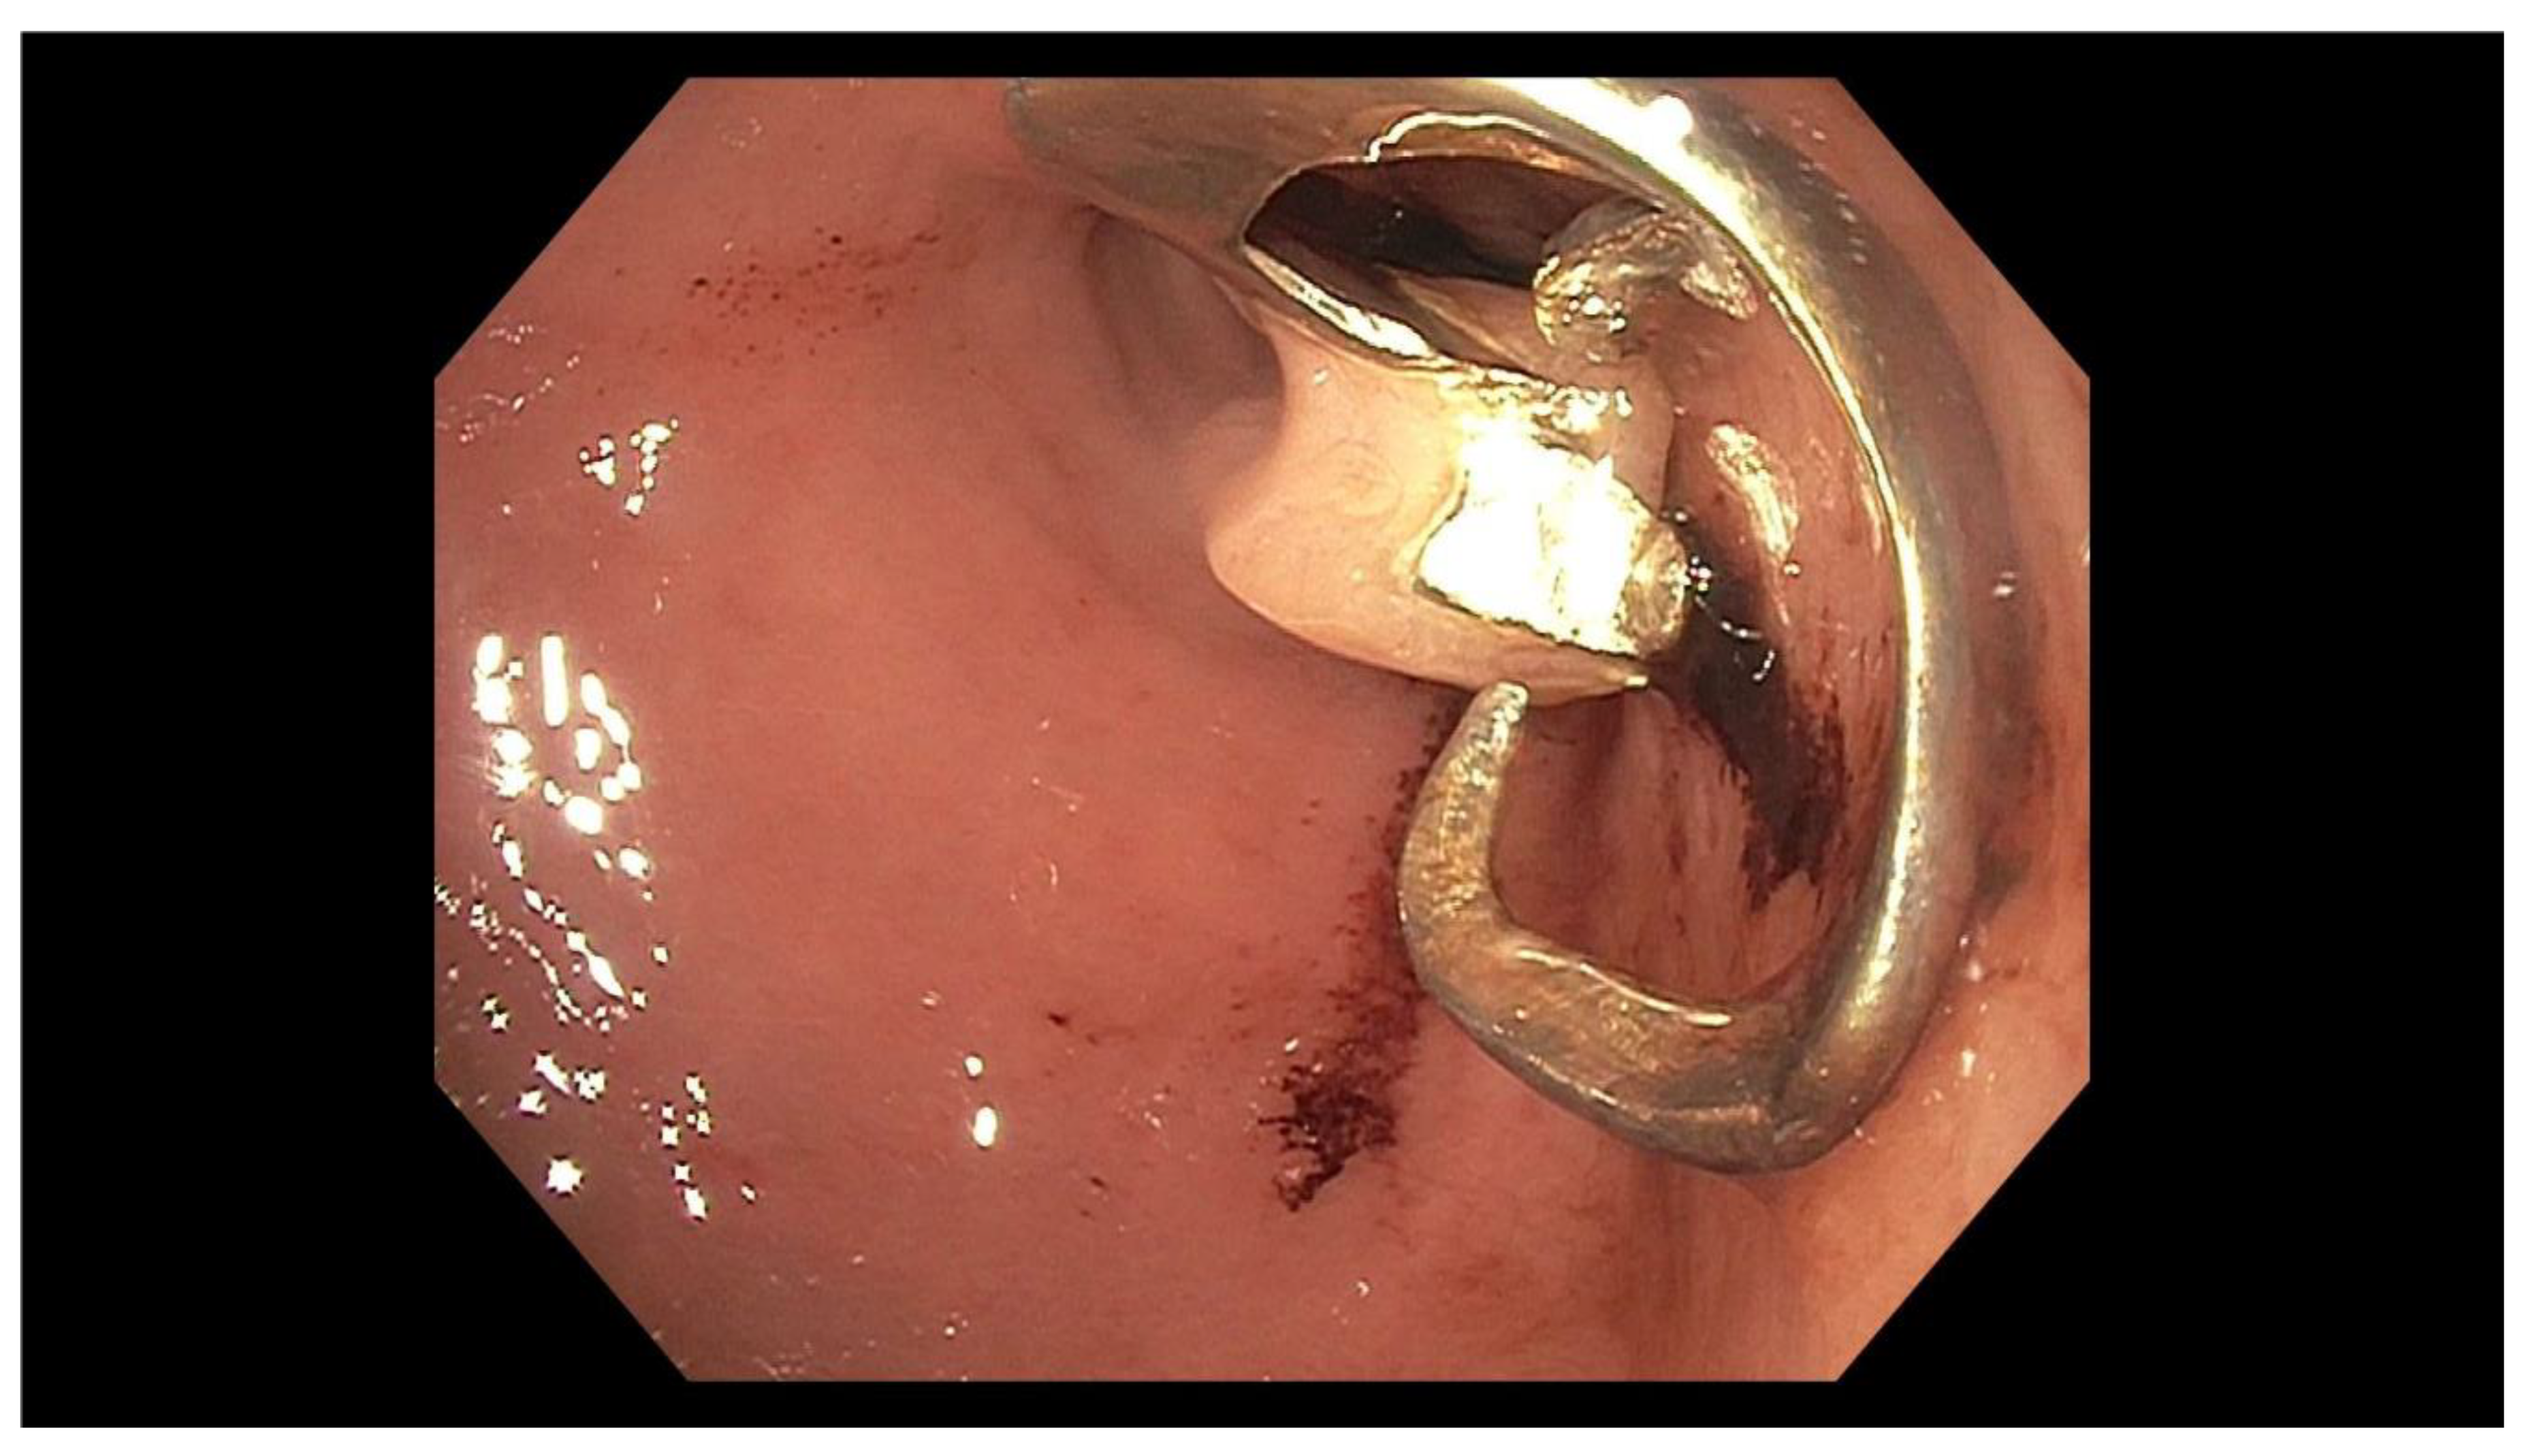

2. Case Report